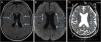

A magnetic resonance imaging (MRI) of the brain revealed bilateral foci of hyperintensity in the periventricular and subcortical white matter of the frontal and parietal lobes on fluid-attenuated inversion recovery (FLAIR) and diffusion-weighted sequence (DWI) images, and foci of hypointensity in the reconstruction of the apparent diffusion coefficient (ADC) maps, characterizing restricted mobility of water molecules, and consistent with true restriction caused by ischemic foci (Fig. 1). The findings were consistent with the PRES diagnosis. Laboratory investigations ruled out infections and metabolic or inflammatory diseases, such as autoimmune ones, and it was impossible to rule out the occurrence of an epiphenomenon.

Magnetic resonance imaging of the brain. (a) FLAIR (fluid-attenuated inversion recovery) showing small foci of hyperintense signal in the periventricular and subcortical white matter of the bilateral frontal and parietal lobes. (b) DWI (diffusion-weighted imaging) showing hyperintense signal from the punctate foci seen on FLAIR (fluid-attenuated inversion recovery), suggesting cytotoxic edema. (c) ADC (apparent diffusion coefficient) MAP confirms the diffusion findings, showing restricted diffusion.